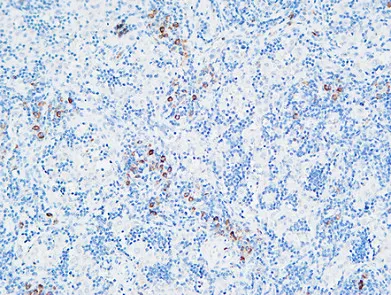

MPO Rabbit Polyclonal Antibody

Cat: APRab14056

Size1:50μl Price1:$118

Size2:100μl Price2:$220

Size3:500μl Price3:$980

Size2:100μl Price2:$220

Size3:500μl Price3:$980